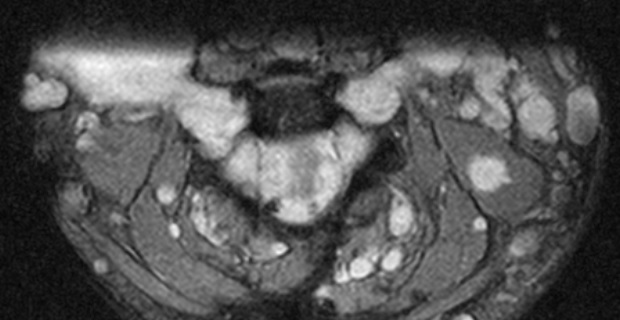

A 67-year old woman with chronic hypertension, hyperlipidemia and diabetes mellitus non-compliant to medication presented with a 10-day history of recurrent visual phenomena in the left visual field. She described stationery multi-coloured flashing lights which decreased in intensity, brightness and size after 3 minutes. She was alert and conscious during attacks. There was no limb jerking. Neurological examination was normal with no visual field defect. Capillary glucose was 28.1 mmol/L, Hba1c 9% and B-hydroxybutyrate < 0.1. She was treated with actrapid 8 units, glipizide 5 mg BD and empagliflozin 12.5 mg OM. Interictal electroencephalogram was normal with no epileptiform activity. Brain magnetic resonance imaging revealed restricted diffusion in the right occipital cortex with corresponding cortical thickening and increased FLAIR signal with subtle hypodensity on GRE sequence. Her visual symptoms improved dramatically with hydration and diabetic control. She was treated with a short course of keppra. One month later repeat MRI brain showed resolution of the DWI and FLAIR abnormalities.

Initial dwi

D